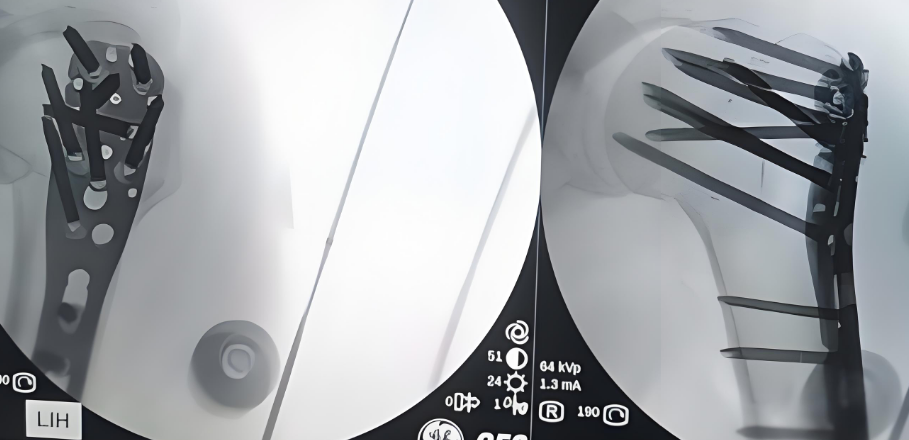

手術治療

術(shu)后圖片

規格:3-13孔,110-290mm